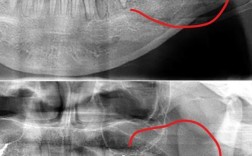

拔牙前准备(1-2周):

拍全景片、头颅侧位片、CBCT评估牙根、牙槽骨及颌骨关系;取研究模型分析牙齿拥挤度;制定个性化方案,与患者沟通拔牙必要性及预期效果。 -